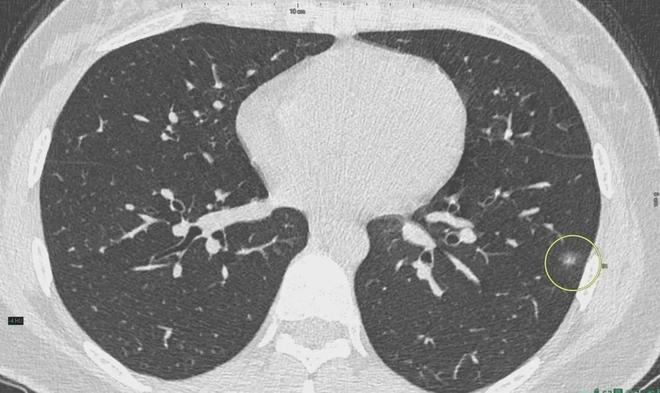

肺結(jié)節(jié)是一種常見的肺部疾病,其發(fā)病率逐年上升,雖然肺結(jié)節(jié)多數(shù)情況下是良性的,但也有可能惡化為肺癌,了解肺結(jié)節(jié)的形成原因?qū)τ陬A(yù)防和治療具有重要意義,本文將為您詳細解析肺結(jié)節(jié)的形成機制。

肺結(jié)節(jié)的形成原因

2、遺傳因素

遺傳因素也是肺結(jié)節(jié)形成的重要因素,研究表明,家族中有肺癌或肺結(jié)節(jié)病史的人群,其患病風(fēng)險較高,遺傳缺陷可能導(dǎo)致肺部細胞異常增生,從而引發(fā)肺結(jié)節(jié)。